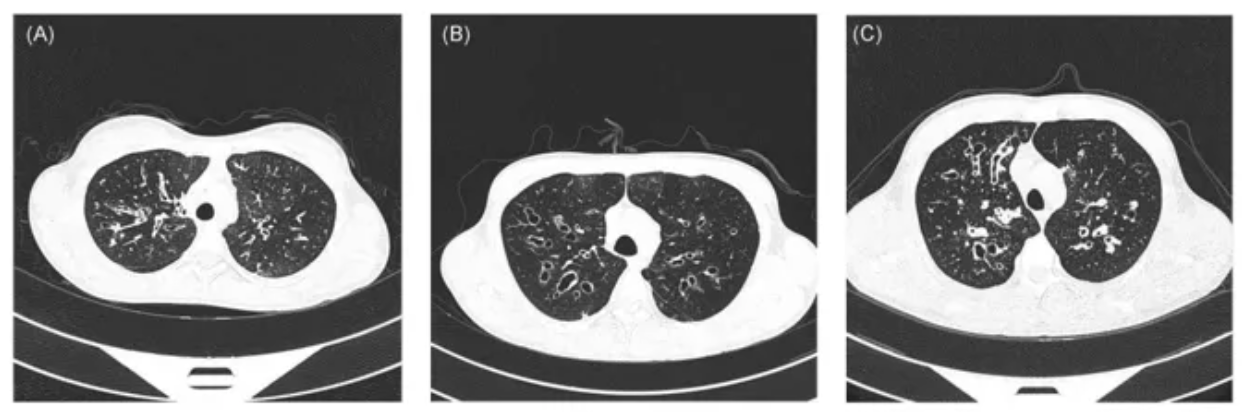

在临床上,如果患者符合以下特征:足月儿发生新生儿呼吸窘迫,早发的支气管扩张,反复不愈的鼻窦炎等症状,就应该考虑进行PCD相关的检查。在询问病史时,以呼吸病史为主,兼顾其他系统。同时应注重询问家族史,家系中有无类似情况。